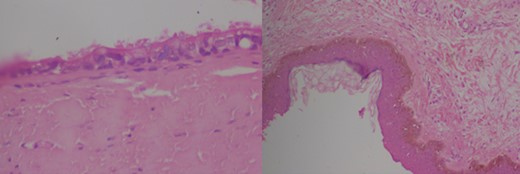

Intra-operatively the cyst was found to extend from the hyoid bone to the supra-sternal notch crossing anterior to the isthmus of the thyroid. Complete excision of the cyst was done. Examination of the excised specimen revealed an atrophied pedicle like extension in its proximal end, arrow in Fig. 1. The possibility of TGDC was entertained and the tissue subjected for histopathology. The pathology slides showed a fibro-collagenous cyst lined by simple cuboidal to columnar epithelium with areas of mononuclear inflammatory infiltrates within the stroma featuring TGDC. (Fig. 2) Patient discharged in the first post operative day and was on regular follow up after wards. After the pathology result the patient was counseled for possible development of Thyroglossal fistula and was on regular follow-up. Six months after the surgery the patient didn’t have signs of thyroglossal duct fistula.

Pathology slides of the specimen confirming the diagnosis of TGDC (high and low power magnification).